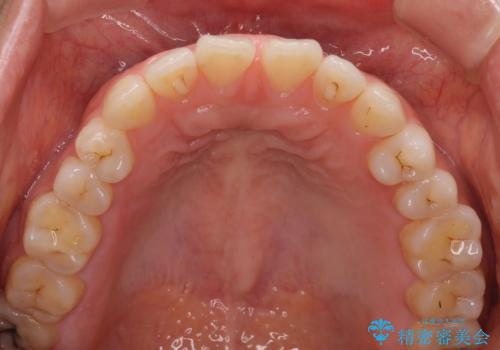

- 上下の前歯の隙間を気にして来院された患者様です。

インビザラインを用い、上下歯列のスペースを閉じていくこととしました。

治療期間中は奥歯がほとんど咬めない状態が続き、食事に大変苦労されました。

最終的には隙間もしっかりと閉じ、奥歯も咬みやすい状態でしあげることができました。